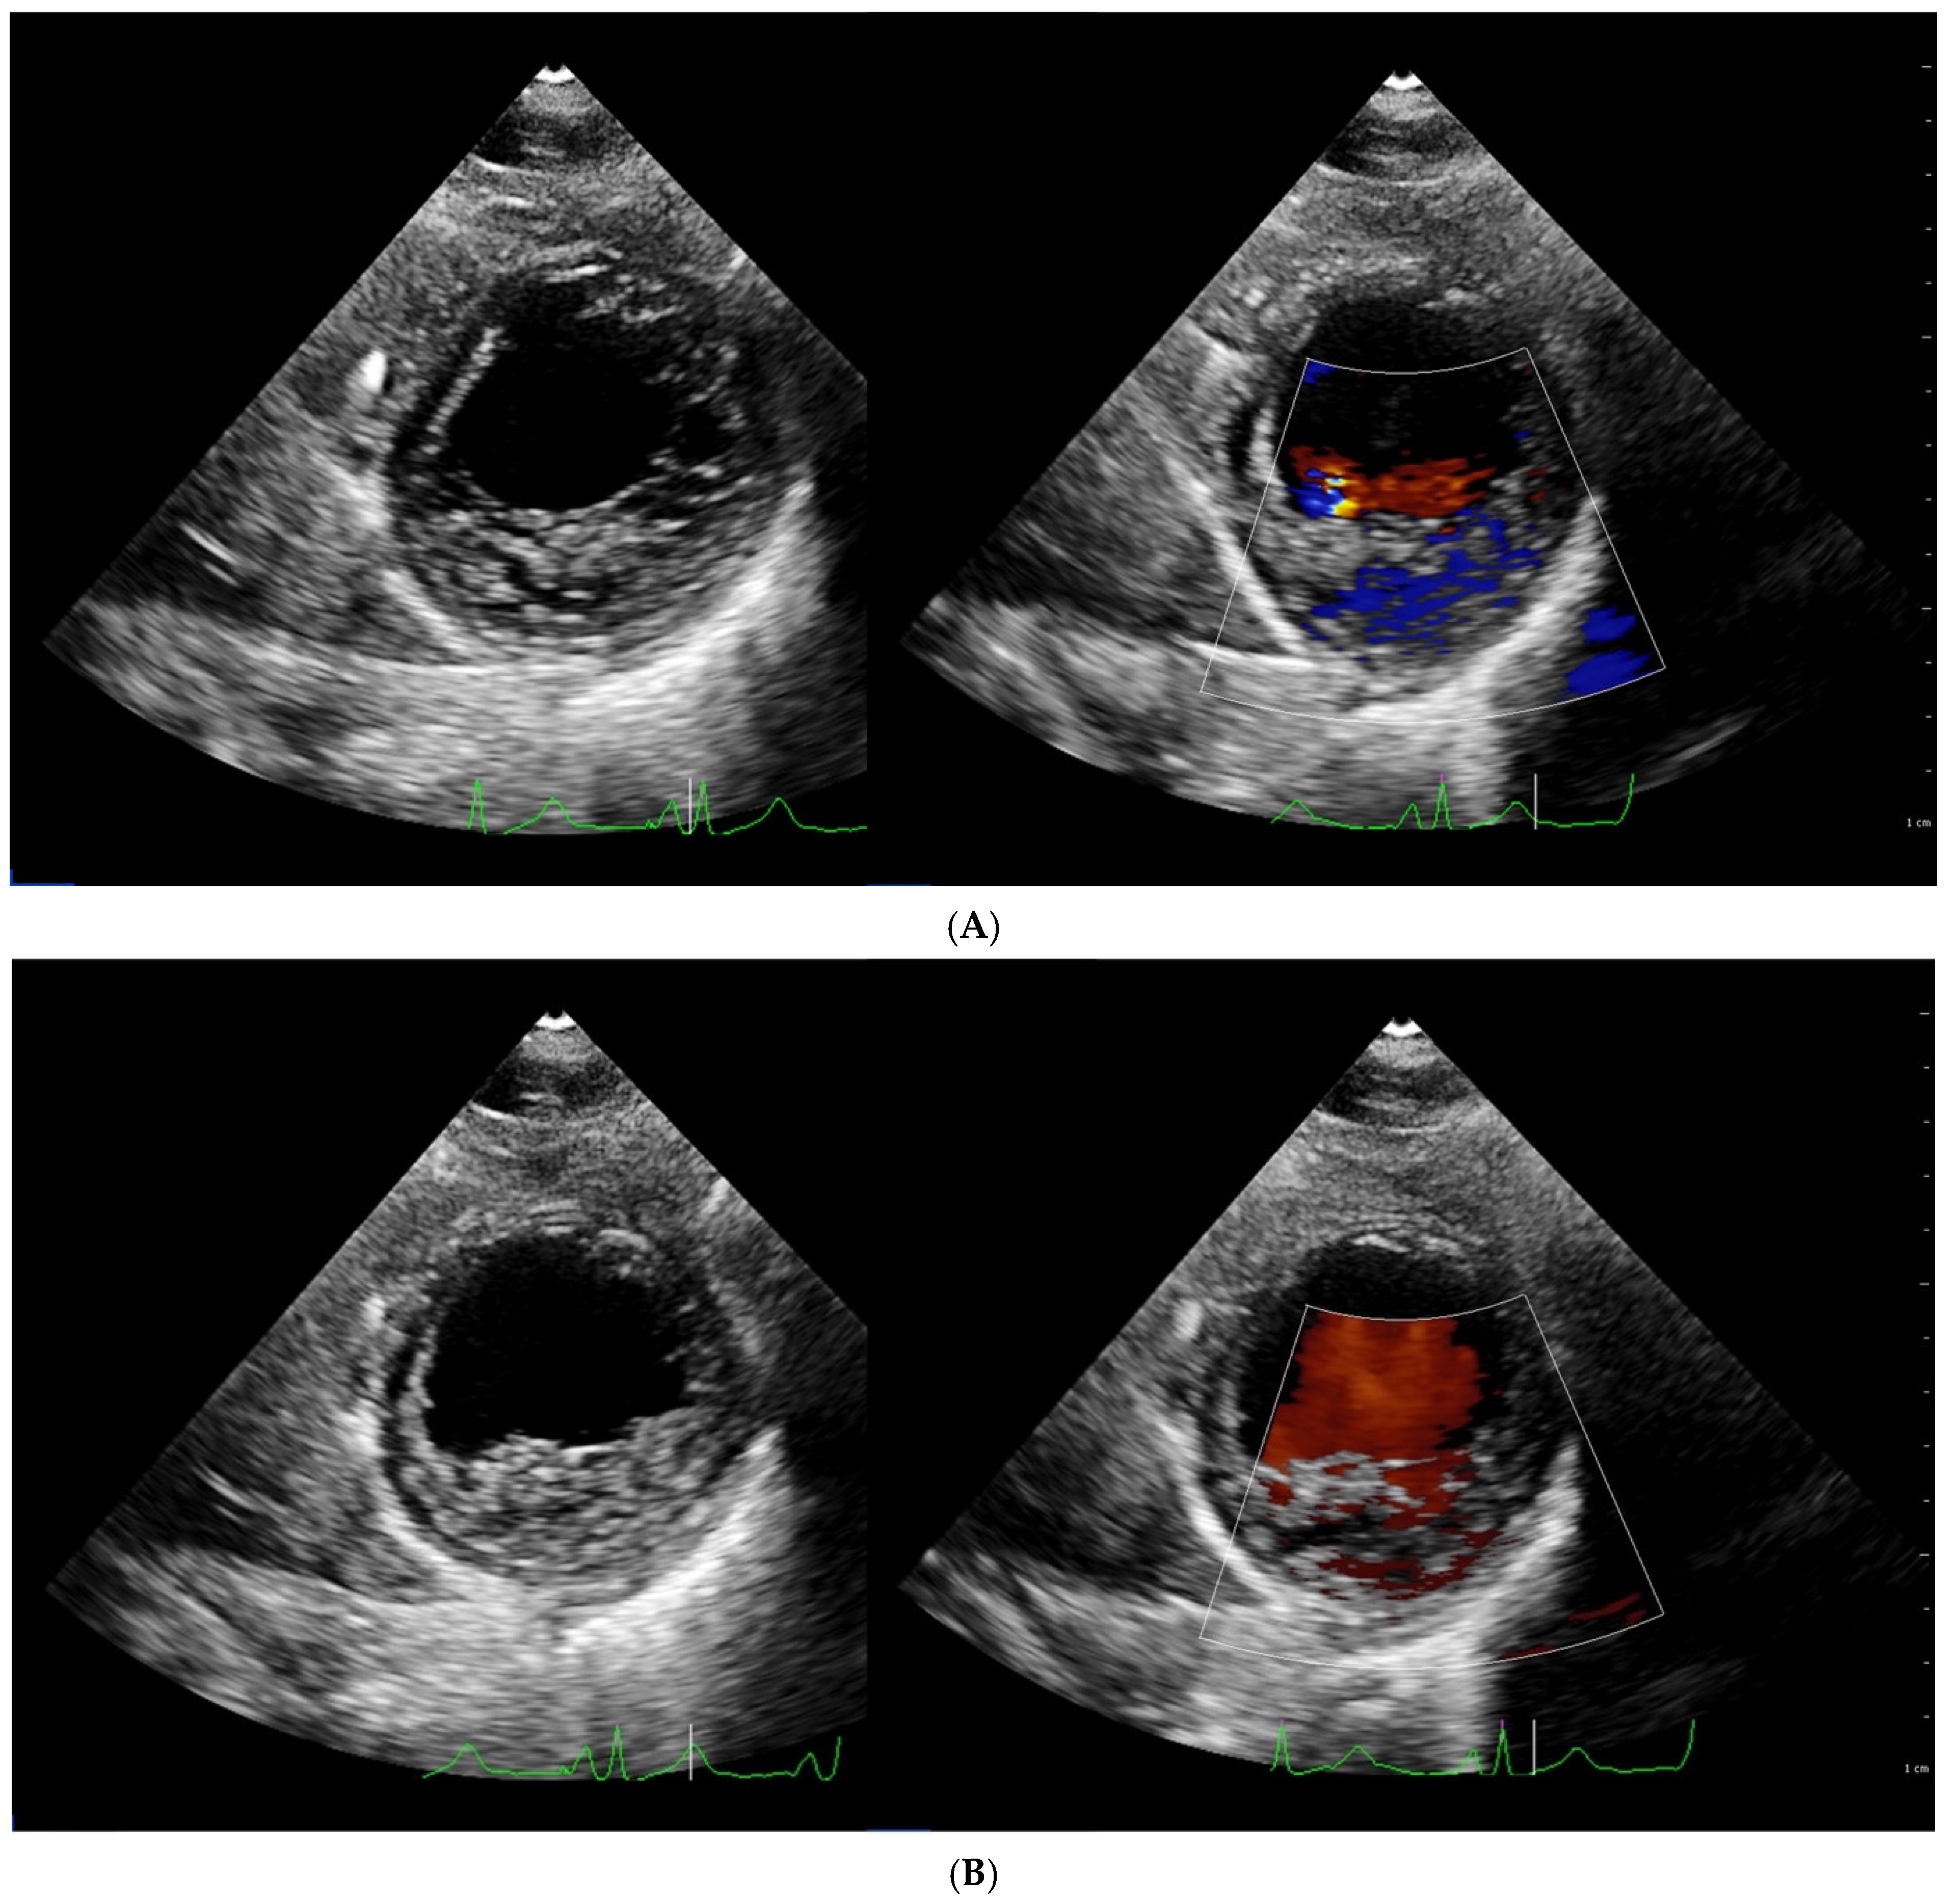

4.1. Echocardiography

| Chin [3] | ECHO | The ratio of the distance from the deepest trabecular recess to the epicardial surface (X) and the distance from the tip of the trabeculation to the epicardial surface (Y) | Long axis, end diastole | X/Y ≤ 0.5 |

| Stöllberger [47] | ECHO | Ratio of compacted and non-compacted endocardium. Presence of at least 3 trabeculations protruding in the left ventricle apically from papillary muscle, presence of the blood flow between trabeculations. | Four chamber, end diastole | NC/C > 2 |

| Jenni [33] | ECHO | Ratio of compacted and non-compacted endocardium. Absence of coexisting cardiac abnormalities, the presence of deep trabeculations, which are filled with blood | Short axis, end systole | NC/C ≥ 2 |